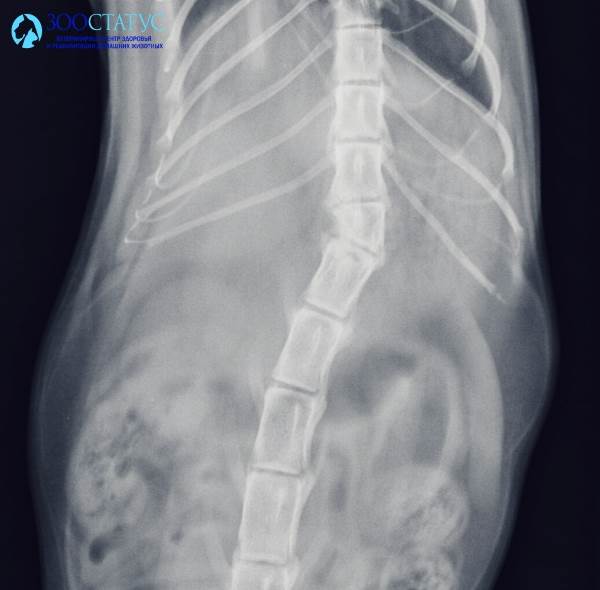

Видео спинальной походки у кота с шестой степенью неврологического дефицита (перелом позвоночника в результате автотравмы).

Спинальная ходьба, или спинальная (рефлекторная) походка - способ перемещения в пространстве кошек с глубоким повреждением спинного мозга (без сохранения глубокой болевой чувствительности), когда движение лап не контролируется головным мозгом, а происходит рефлекторно.

У животных с 6 степенью неврологического дефицита отсутствует глубокая болевая чувствительность, и головной мозг не может управлять моторной функцией конечностей. В норме верхний мотонейрон, расположенный в головном мозге, посылает импульсы нижнему мотонейрону (нервные клетки спинного мозга, ветви от которых ведут непосредственно к мускулатуре), регулируя последовательность сокращения мышц. При патологии, нарушающей эту взаимосвязь, необходимые для локомоции (движения) центры сохраняются, эти функции выполняет спинной мозг и периферическая нервная система. Путем стимуляции рефлексов и наработки паттерна шага можно выработать у животного ритмическое стереотипное шагание. Спинальная походка выглядит гораздо более неуклюжей, чем нормальная, у животного могут быть проблемы с координацией и тонкими движениями, однако автономная мобильность значительно улучшает качество жизни парализованного животного.